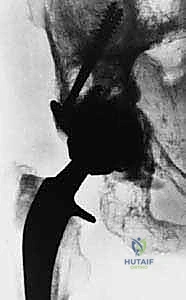

- إدارة خطر النزيف (Embolization): بعض الأورام مثل سرطان الكلى والغدة الدرقية تكون عبارة عن كتل دموية نابضة. لتجنب النزيف القاتل أثناء الجراحة، يتم إجراء "إصمام وعائي" (Angioembolization) قبل 24-48 ساعة من العملية لقطع الدم عن الورم.

- اختيار نوع المفصل الاصطناعي: بناءً على صور الأشعة المقطعية، يحدد الجراح نوع المفصل. في حالات الأورام، غالباً ما تُستخدم مفاصل ذات جذوع طويلة (Long-stem prostheses) لتجاوز منطقة الورم وتثبيت المفصل في العظم السليم أسفل الآفة. كما تُستخدم تقنية الأسمنت العظمي (Bone Cement - PMMA) بكثافة لتوفير استقرار فوري للمفصل والسماح للمريض بالمشي في اليوم التالي.